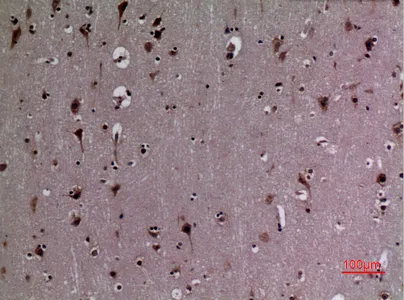

CD68 Rabbit Polyclonal Antibody

Cat: APRab08436

Size1:50μl Price1:$118

Size2:100μl Price2:$220

Size3:500μl Price3:$980

Size2:100μl Price2:$220

Size3:500μl Price3:$980